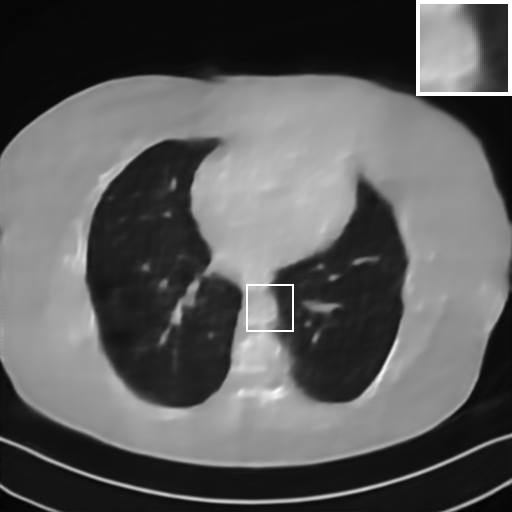

Fig. 4 presents the reconstruction results and residual images obtained by different methods for limited-angle reconstruction. As can be seen, the learning-based methods outperform the direct method and TV model, which exhibit serious artifacts in the missing angle region. Although the denoiser introduced by the FBP-Unet can somehow deal with the noises, the result still presents obvious artifacts. Compared to the SIPID, PD-net and FSR-nets, our LRIP-net1/2 can better preserve the image details and edges with less information left in the residual images. Thus, both the quantitative and qualitative results confirm that the low-to-high double-resolution strategy can improve the reconstruction accuracy for the limited-angle reconstruction problem.

We observe that the low-resolution image prior plays an important role in our method. More specifically, we compare the results of our LRIP-net with respect to different low-resolution priors, which are obtained by down-sampling rate of 1/2, 1/4, and 1/8, respectively. As can be seen in Table III, the best reconstruction results are obtained with the image prior reconstructed by the down-sampling rate of for 150∘, 120∘ and 90∘ limited-angle reconstruction. The visual comparison based on different image priors are also provided in Fig. 5, where obviously less artifacts are left in the reconstruction image by LRIP-net1/8. By comparing the running time, it is easy to see that the smaller the low-resolution image prior, the faster the LRIP-net works.